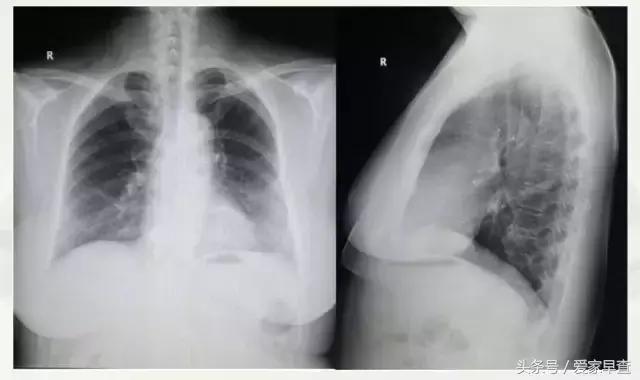

53岁女性正侧面胸片

我们先来看一个胸片(上图),这是胸部的正侧位。这个人是53岁的女性,她是在查体的时候先拍的胸片。其实拍胸片时并没有发现什么问题,这是一个胸部的正侧位,是两张片子。

通常在体检中心或者在体检机构进行体检的时候,都是只拍一个胸部的正位片。这是符合体检的要求,体检都是只拍一张正位片。但是这个人是因为他有其他的症状去医院拍片子,常规拍了一个正侧位。在这个片子上,我们并没有看到什么问题。